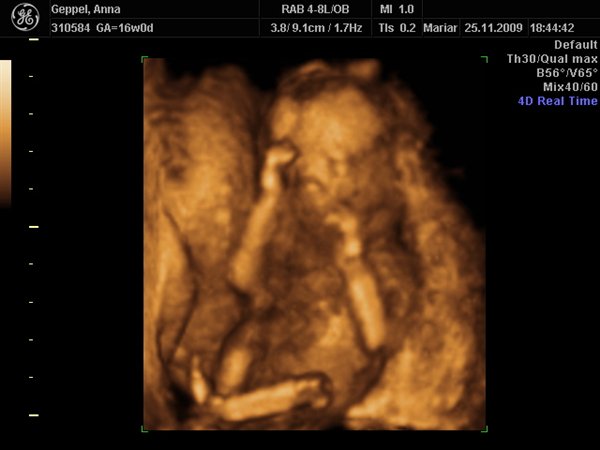

Det sidste er ret utydeligt, men han har vendt ryggen til og holder en hånd til det ene knæ.